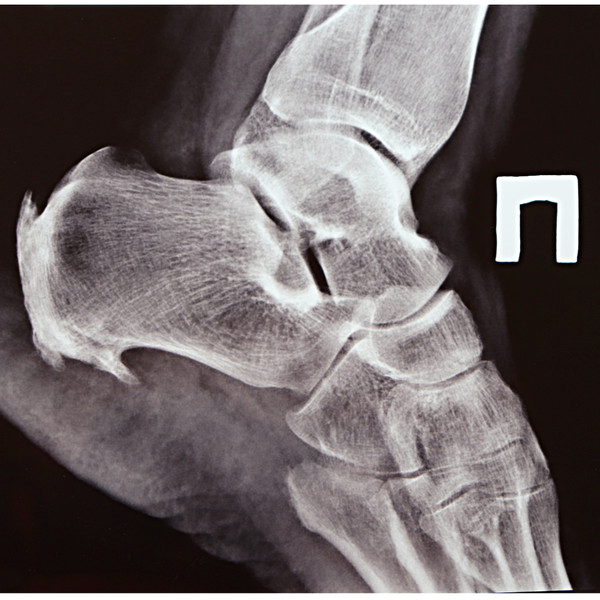

Bone SpursBone Spurs

Bone spurs are bony growths that develop along joints or the heel and are often caused by pressure, arthritis, or chronic inflammation. While not always painful, they can lead to discomfort, stiffness, or nerve irritation depending on their location. Early diagnosis and treatment—ranging from orthotics and physical therapy to advanced in-office options—can help relieve symptoms and prevent further complications.